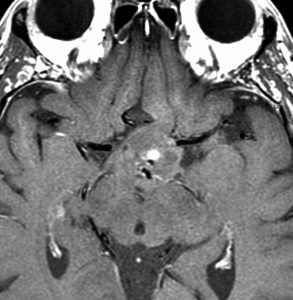

2歳の時に歩行障害で転倒しやすくなって発症しました。巨大な小脳虫部の毛様細胞性星細胞腫です。後頭下開頭で亜全摘出して,翌年,残っていた小さな残存腫瘍を全摘出しました。

cerebellarpilo3cerebellarpilo4

16歳になってとても元気に学校へ通っています。こんな小脳でもちゃんと歩けるようになります。残っているわずかな小脳機能を手術で守ることはとても難しいと言えます。